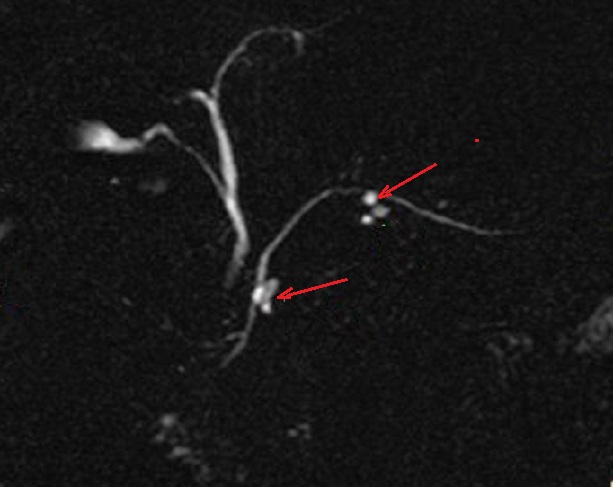

Sus les coupes IRM pondere

sur T2 Image radiolofique des TIPMP de type canaux

secondaire sont des kystes unique ou multiple

arondie ou ovalaire polylobulaire de fortement

hyperintense et comunication souvent avec canal

principale CPP ( fleche rouge ) . Image radiologique

IRM ponderation sur T2 , en coupe axiale |